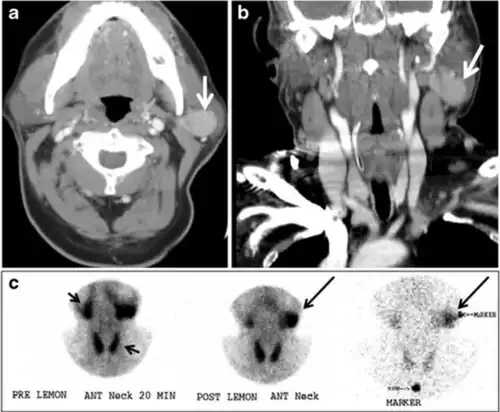

Fig. 17. Ectopic thyroid on the left parotid gland with a palpable left parotid mass in a 69-year-old male patient. a, b Axial and coronal enhanced neck CT scan demonstrates well-defined homogeneous enhancing mass (white arrows) within the left parotid gland with preserved surrounding fat planes. It also shows a normal thyroid in normal position in the lower neck. c Image taken 20 minutes after 5 mCi injected Tc99m-Pertechnetate shows normal thyroid uptake of tracer and physiological uptake in the salivary glands (short black arrow). There is a distinct focus of abnormal tracer accumulation in the left parotid/submandibular region. Patient was given lemon juice with evident normal washout from the salivary glands and relative retention by this abnormal focus (long black arrow).[1]